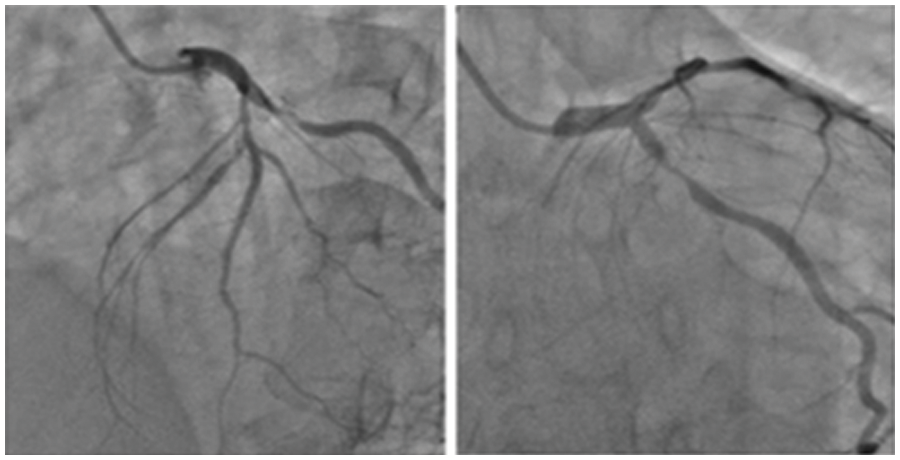

Figure 3: Sample input images containing coronary angiograms

The data consisting of 28 images of coronary angiograms are taken from reputed medical institutions. We used the Keras Image data Generator to virtually generate more images using different forms of rotation, skewing etc. Since our batch size is 500, for every epoch 500 images are generated. In 10 epochs, the number of images is 500 * 10 = 5000. These images have been tested with various image processing techniques to segment the image. Some of the notable techniques include log transformation, contrast stretching with histograms and thresholding. The techniques previously proposed by researchers did not provide satisfactory results. Hence, in this methodology, a semi-supervised-based technique with neighborhood contrasting is used to generate annotations for the image. Fig. 3 depicts the sample input images of coronary angiograms and shows the coronary branches in the coronary angiogram. From this figure, Left Main (LF), Left Anterior Descending (LAD), Left Circumflex (LCx), Obtuse Marginal (OM), Diagonal (D), Septal branch, Right Coronary artery (RCA), Acute Marginal, Posterior Left ventricular branch (PLV), Posterior Descending Artery (PDA) can easily be identified by any experienced cardiologist or cardiac surgeon.